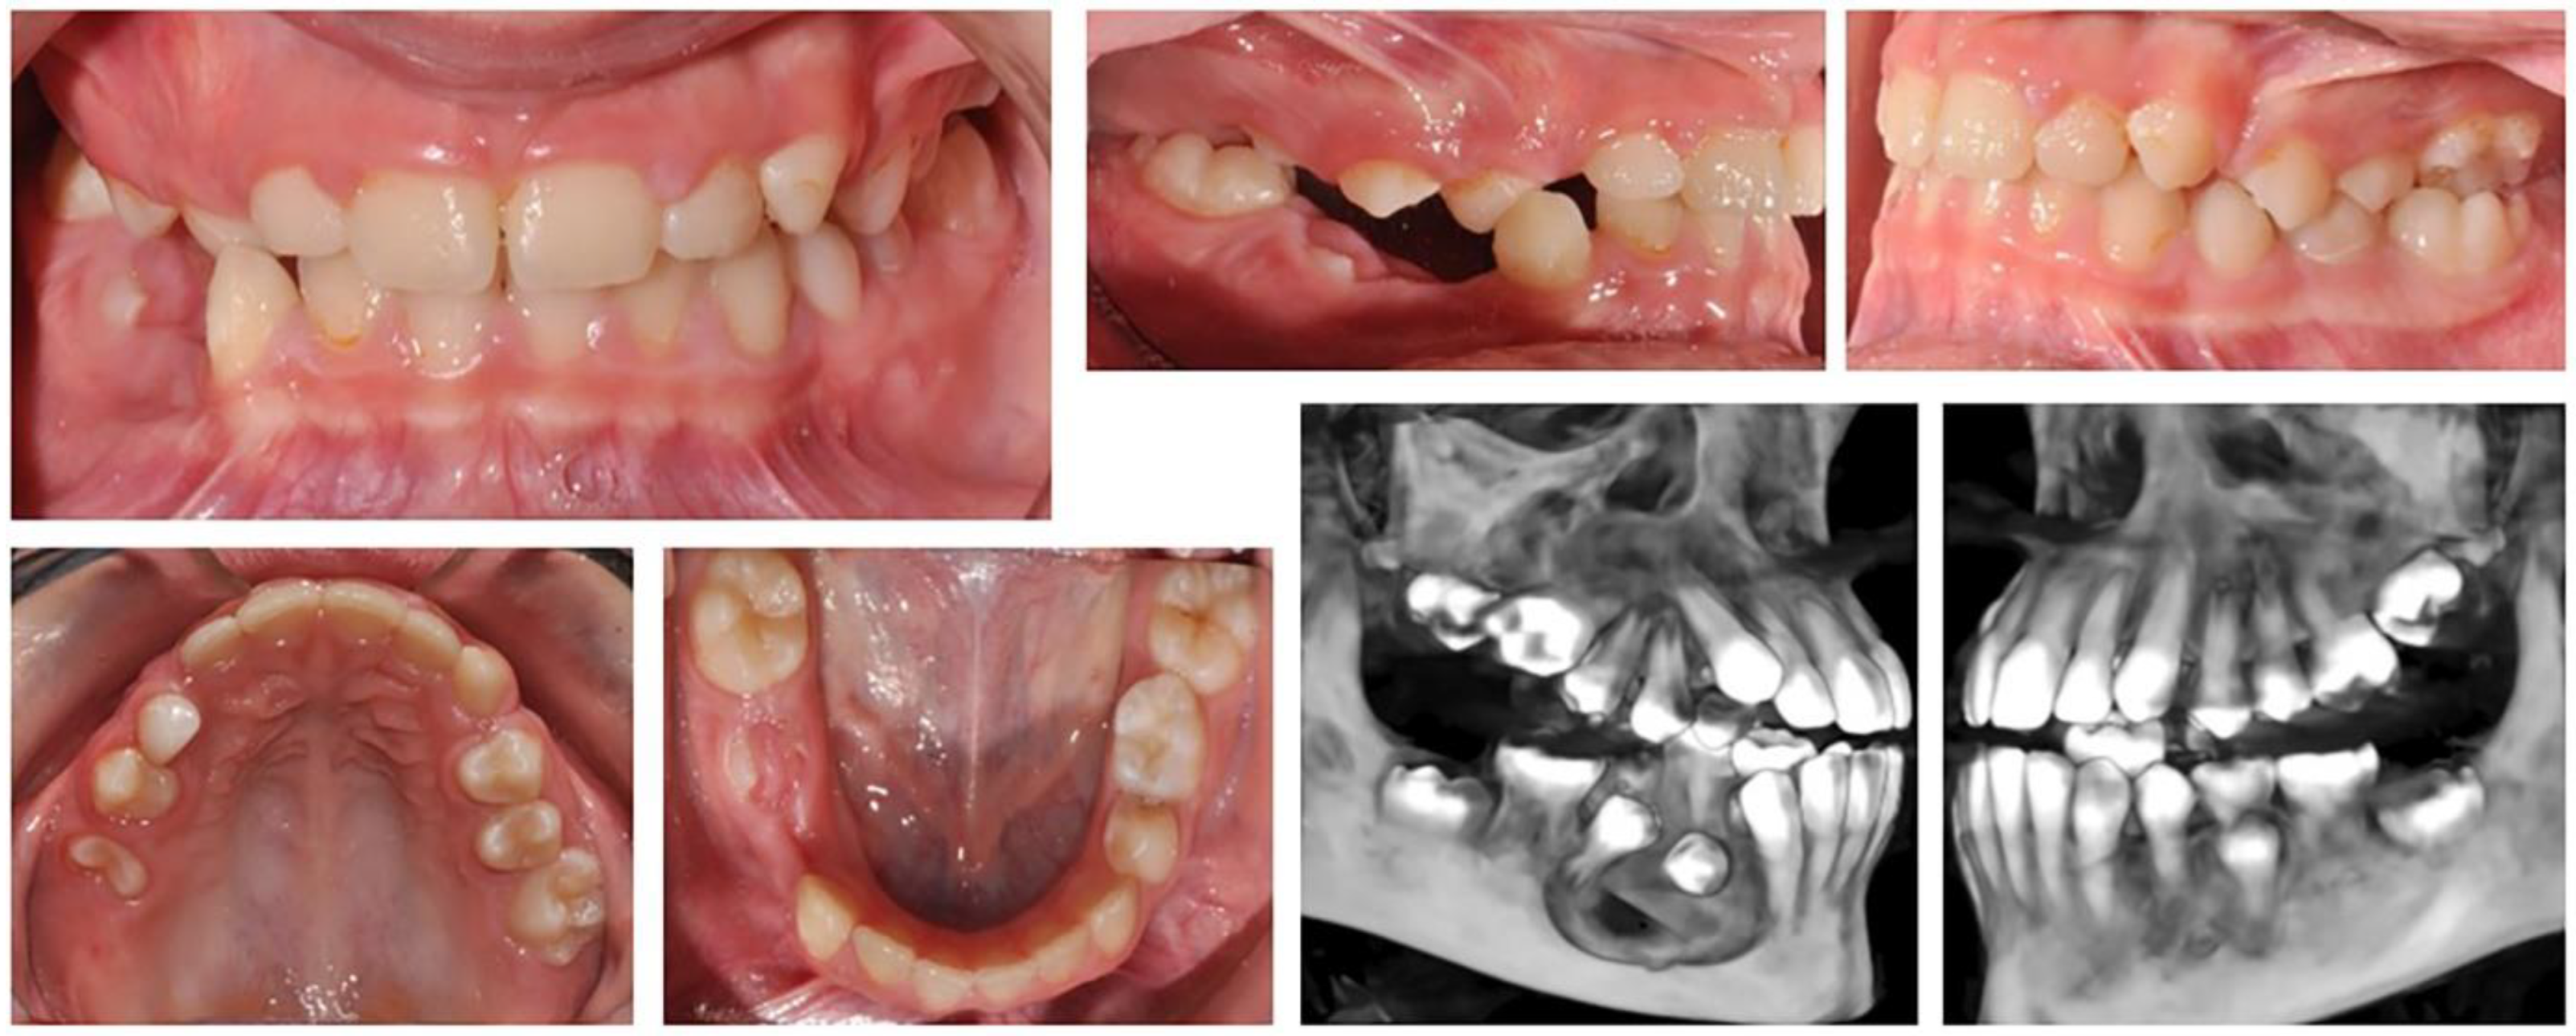

2.2.3. Clinical Case 3–Treatment of Patient with Cleft of the Hard Plate

A 17-year-old female patient with a surgically repaired cleft of the hard palate was included. The patient’s complaint was worsened aesthetics. The upper frontal teeth were retruded and extruded; thus, the bite was deep. During the first clinical examination, a reduced perimeter of the upper dental arch was found, crowding was observed both in the frontal and in the middle segment (in the premolar area) and the shape of the dental arch was trapezoidal (Figure 6).

In orthodontic analysis, the count of medio-distal (MD) diameters of ten teeth from 15 to 25 was MD (15–25) = 63.9 mm. The dental arch perimeter was P (15–25) = 53.83 mm. The discrepancy of MD-P = 10.07 mm was observed (Figure 7). The treatment goal was to provide space in upper dental arch through the extraction of first premolars 14 and 24. The count of first premolar space was almost equal to the discrepancies in perimeter. The upper-right lateral incisor was located on the palate and that resulted in the canine being in contact with the central incisor. The lateral incisor should be included in the dental arch. During the distal movement of the canine, there was a risk of the medialisation of teeth in distal segment and of lost anchorage. Therefore, the use of PDaA was the appropriate decision.

Figure 6. Initial status of patient with a surgically repaired cleft of the hard palate.